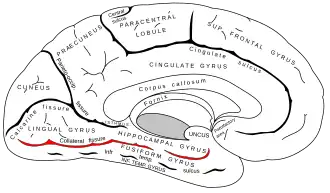

Medial surface of left cerebral hemisphere. (Collateral fissure labeled at bottom left.) | |

The collateral fissure is a large sulcus on the tentorial surface of the cerebral hemisphere and extends from near the occipital pole to within a short distance of the temporal pole. It is also known as the medial occipitotemporal sulcus.[1]

Behind, it lies below and lateral to the calcarine fissure, from which it is separated by the lingual gyrus; in front, it is situated between the parahippocampal gyrus and the anterior part of the fusiform gyrus.